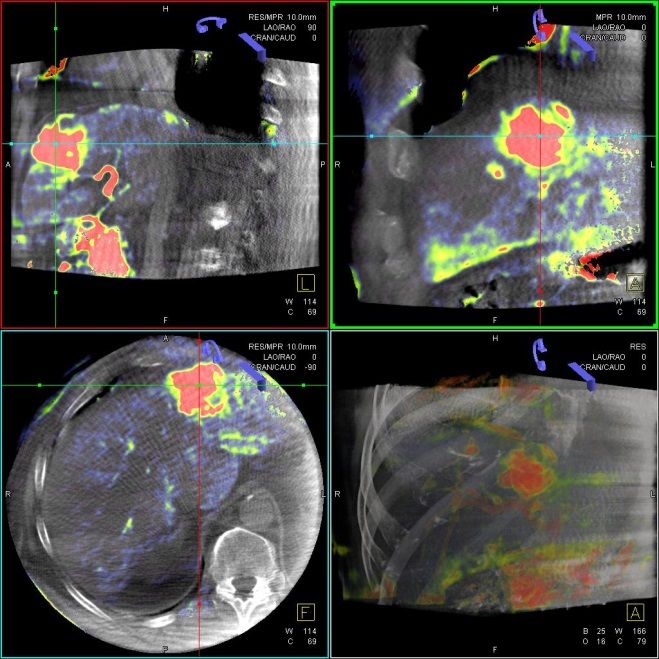

Bei der perkutanen Thermoablation von Nierentumoren werden spezielle Applikatoren unter CT- oder MRT Bildgebung in den Zieltumor eingebracht. Durch Hitze wird der Tumor zerstört.